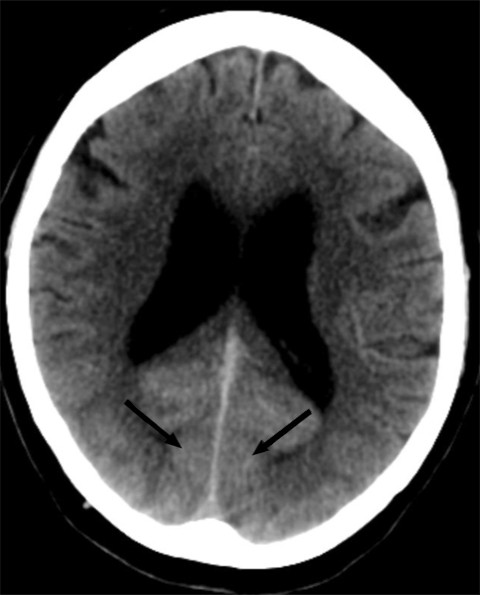

30 minutter etter at hun ble akutt blind, ble det tatt CT caput og CT-angiografi av intrakraniale arterier. CT caput viste utbredt diffus kontrastoppladning i synsbarken (oksipitalt) bilateralt, men ingen blødning eller infarkt (figur 1). CT-angiografi viste ingen karokklusjon eller karspasmer. Som forventet ved en kranial dural arteriovenøs fistel var det økte kartegninger og arterialisert kontrastfylning i durale vener.

MR caput (T1- og T2-vektede sekvenser, FLAIR-sekvenser og diffusjon med ADC-verdier (apparent diffusion coefficient)) utført rett etter CT-undersøkelsen viste som tidligere uspesifikke T2- høysignal lesjoner, men ingen nytilkomne forandringer (figur 2). Det var ingen diffusjonsrestriksjon, som er forventet ved ferskt hjerneinfarkt (3).

På pasientens CT-bilder var det retensjon av kontrast i synsbarken på begge sider. CT-bildene var gjort uten kontrast, så den synlige kontrasten måtte være fra konvensjonell cerebral angiografi gjort to timer tidligere. CT-angiografi viste åpne kar. På MR var det ingen nytilkomne signalforandringer. De kliniske symptomene sammen med bildefunnene passet dermed ikke med cerebral iskemi på bakgrunn av tromboembolisme eller karspasmer.

Dette er en eksklusjonsdiagnose. MR caput og eventuelt CT caput med CT-angiografi er indisert for å utelukke blødning eller iskemisk årsak til synsaffeksjon. MR kan være negativ eller vise høysignal på T2- og FLAIR-signaler som ved vasogent ødem. CT kan vise normale funn eller kontrastoppladning oksipitalt. CT-angiografi fremstiller åpne kar uten spasmer.